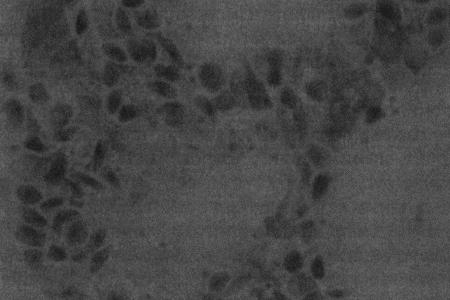

О повышении концентрации эстрогенов можно судить по таким изменениям, как гиперплазия и гипертрофия вагинального эпителия, ороговение и эксфолиация его клеток. Вагинальная цитология позволяет выявить характерные изменения, служащие индикатором активности этого гормона. На стадиях цикла, протекающих на фоне минимальной эстрогенной активности (анэструс, метэструс, препубертатный период), в вагинальных выделениях у сук преобладают парабазальные клетки (фиг 3.1), которые имеют округлые очертания и низкий объем цитоплазмы по отношению к ядру. Под влиянием эстрогенов развивается гипертрофия эпителиальных клеток влагалища, затрагивающая мелкие промежуточные клетки (они крупнее парабазальных, с округлыми очертаниями и относительно более высоким соотношением ядра к цитоплазме; фиг. 3.1–3.3), крупные промежуточные клетки (полигональные клетки с неповрежденным ядром; фиг. 3.3) и поверхностные клетки (сходные с крупными промежуточными клетками, но, как правило, безъядерные или с пикнотичным ядром; фиг. 3.4). Число поверхностных ороговевших безъядерных клеток возрастает в фазе проэструса, сохраняется постоянным в течение эструса (фиг. 3.4) и резко уменьшается к моменту его окончания. Стремительное сокращение (более чем на 20 %) количества этих клеток свидетельствует о наступлении первого дня метэструса (фиг. 3.2). Характерно, что к этому моменту вагинальные выделения просветляются и уже не содержат ни органических остатков, ни окрашенной слизи. Повышенное содержание лейкоцитов может указывать на наличие инфекции, а присутствие аномальных клеток — на опухолевый процесс. Повышенное содержание нейтрофилов, наблюдающееся в начале метэструса (фиг. 3.1 и 3.5), считается нормой и не является признаком патогенной инфекции.

Фиг. 3.5.

Начало метэструса у суки. В мазке вагинальных выделений присутствуют нейтрофилы и мелкие промежуточные клетки (окрашивание мазка Diff-Quik®) (см. Приложение)